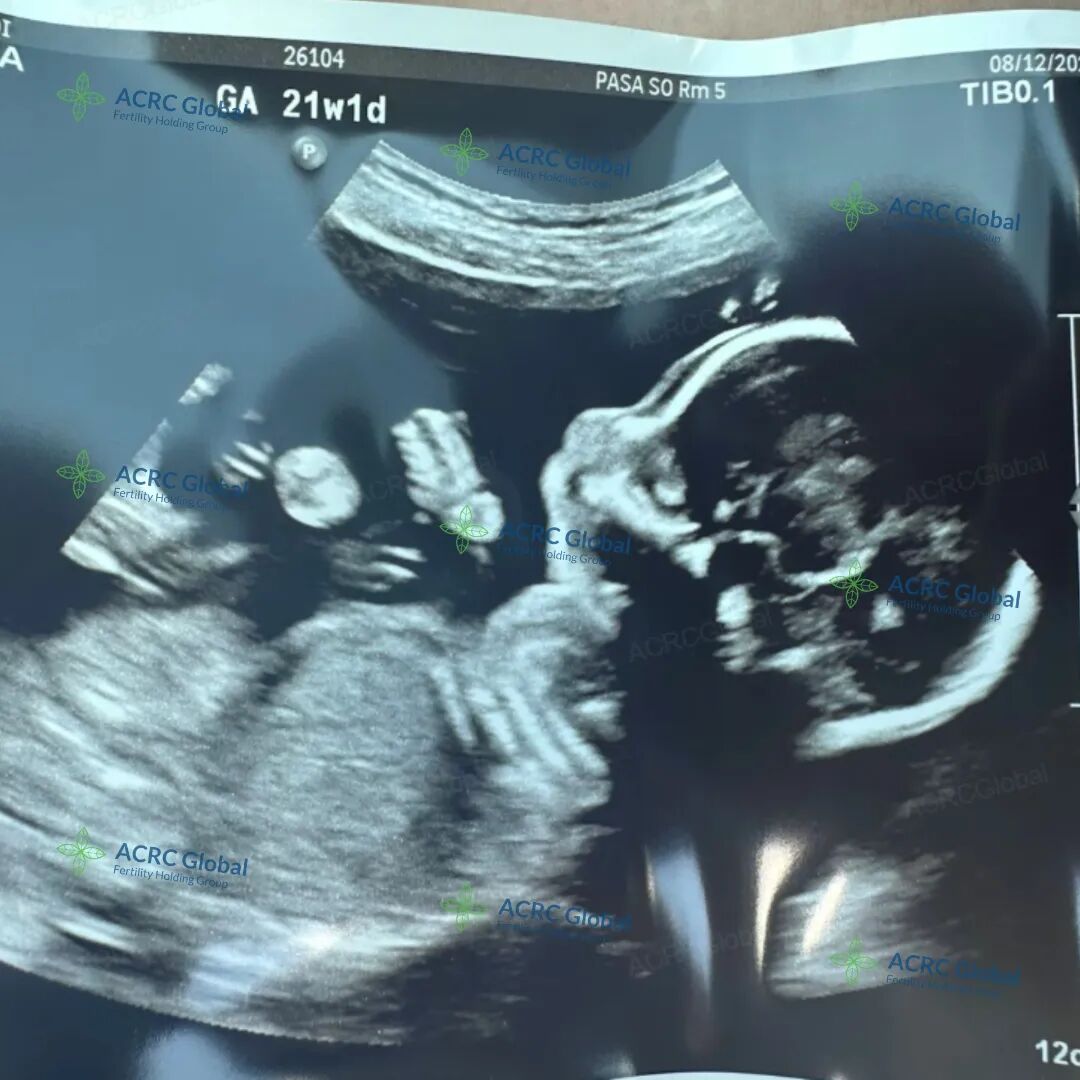

爱妈H也顺利进入了孕中期,目前宝宝已经21周大。宝宝大约27厘米长,重约360克,像一个胡萝卜大小。这个阶段是宝宝稳定的发育期,各项身体功能和感官正在逐步完善。准父母对即将到来的男宝充满了期待!